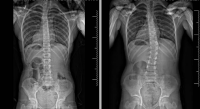

“So, we took the chance to see if therapy would work. Zara did rigorous PT for 4-5 months and when we returned, the curve went from 30 degrees to about 15 degrees,” said Sabrina. “The difference was striking on the x-rays, it brought me to tears. We consider it a miracle and finding someone like Dr. Vitale, who took that leap of faith to wait before bracing, was really amazing.” The family and Zara continue to monitor her spine closely. “We are so watchful, and never take her progress for granted. I know we are not out of the woods, but we hope things continue to progress the right way. We want to make sure Zara is headed in the right direction.”